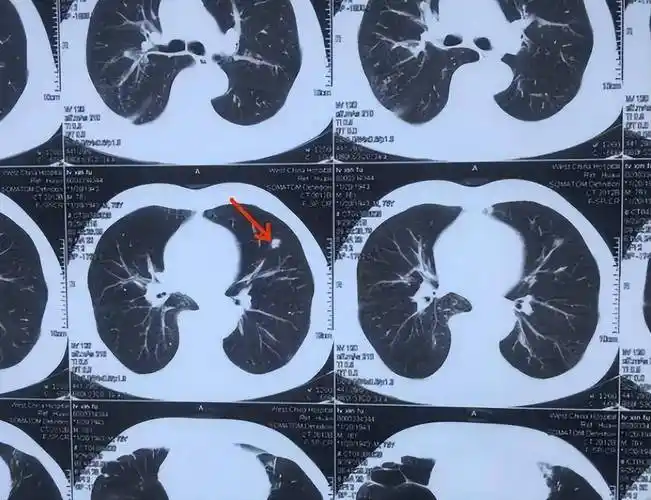

几天后,王大叔的ct结果出来了,果然被确诊为早期肺癌.